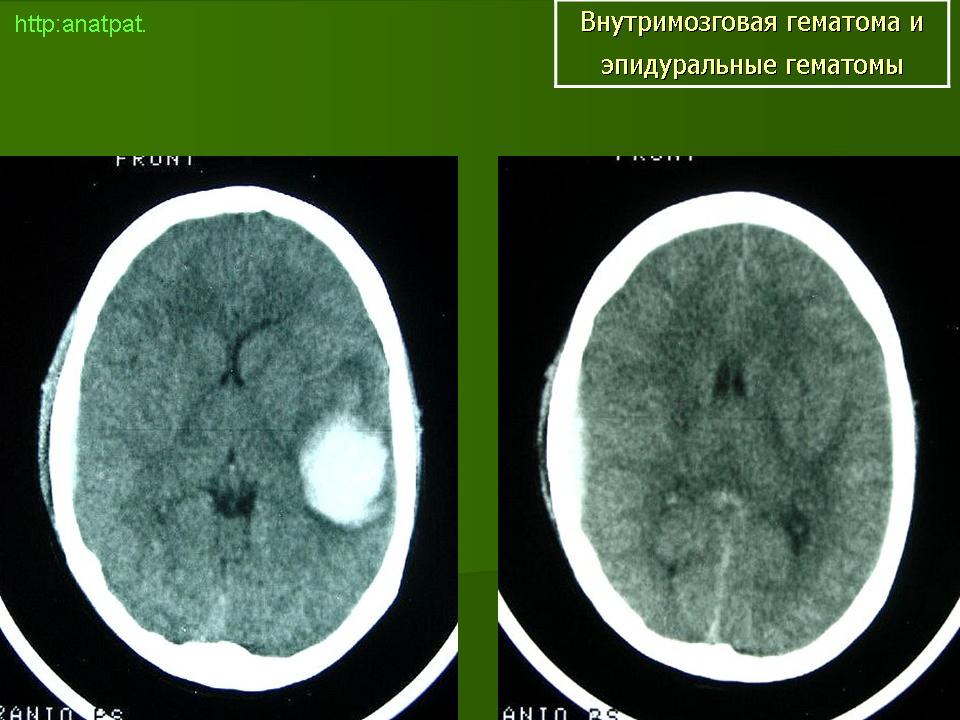

Внутримозговые гематомы